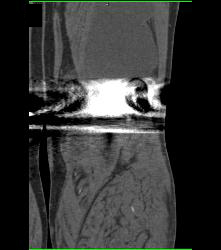

Bakers Cyst